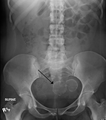

A small uterine fibroid seen within the wall of the myometrium on a cross sectional ultrasound view- Two calcified fibroids (in the uterus)